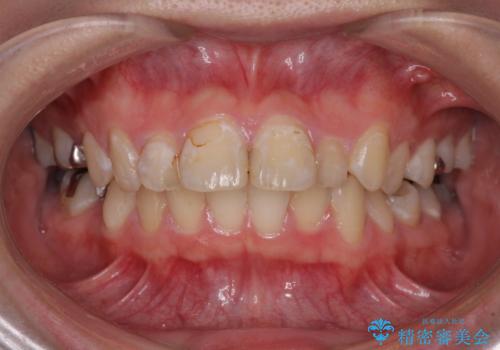

- 上の前歯の出っ歯とでこぼこの歯並びを気にして来院された患者様です。

上下顎歯列ともに前方に突出していましたが、上顎歯列がより前方位にあったため、上顎左右は第1小臼歯を、下顎左右は第二小臼歯を抜歯することとしました。

目立たないワイヤー装置にて抜歯矯正を行うこととしました。